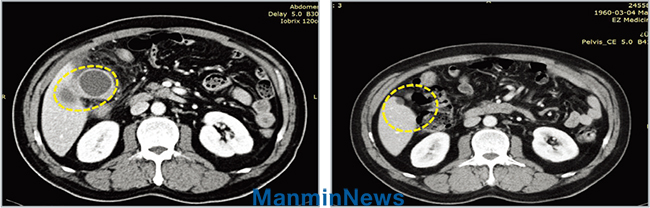

Компьютерная томография

▲ До молитвы: у него некроз желчного пузыря, перфорация и сильный воспалительный процесс ▶ После молитвы: его желчный пузырь пришел в норму после молитвы